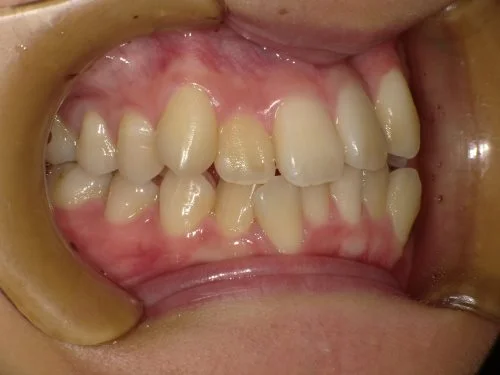

<症例7>歯がガタガタで噛み合わせが悪くお悩み

抜歯無し・マウスピースのみで矯正した症例です。

もともと歯列弓が非常に狭く、V字に近い形をしていたので噛み合わせも非常に不安定でした。

また、下顎前歯部がかなり上の方に生えていたため、下の前歯が上の前歯を突き上げてしまい出っ歯の状態になっていました。

現在では見た目はもちろん、臼歯の噛み合わせも改善しております。

患者様と症状

主訴:歯のガタガタ、噛み合わせが悪い

性別・年齢:20代女性

問題点:叢生(重度)、V字歯列弓、ディープバイト

診断:前歯部の叢生を伴うアングルⅠ級、骨格性Ⅰ級の不正咬合

主なリスク:臼歯の移動に伴い一時的に咬合しにくくなる、歯肉退縮

症状:叢生(そうせい) 過蓋咬合(かがいこうごう)

治療内容

治療期間:1年10ヶ月

治療費用:990,000円(税込)

プラン:Full2プラン

抜歯:無し

再診治療費:無し

追加治療費:無し

保定装置費:無し

治療前後の写真